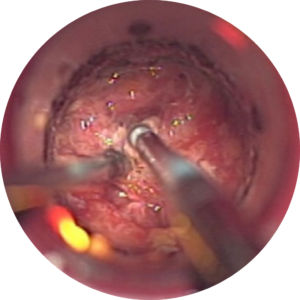

iBur in action

I like the fact the shaft is integrated. The irrigation component is nice... it did not get hot at all."

- Spine surgeon